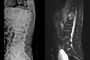

인제대학교 부산백병원(원장 양재욱)이 최신형 컴퓨터단층촬영장치(CT)와 자기공명영상장치(MRI)를 도입해 심뇌혈관 및 응급질환 진단 역량을 한층 강화했다. 특히 CT는 응급의료센터에 설치돼 뇌졸중과 심근경색 등 ‘골든타임’이 중요한 심뇌혈관 환자의 신속한 진단에 활용한다. 이는 최근 보건복지부가 지정한 ‘지역 심뇌혈관질환센터’ 운영에 더해 지역 내 심뇌혈관 응급의료 체계를 더욱 강화할 전망이다. 부산백병원은 3월부터 두 장비 모두 본격 운영에 들어갔다. CT장비 ‘Revolution APEX Elite’는 초고속 회전 기술과 넓은 검출 범위를 갖춘 최첨단 장비로, 기존 CT보다 빠르고 정밀한 영상 촬영이 가능하다. 0.23초의 초고속 회전 속도와 160mm의 넓은 촬영 범위를 갖춰 매우 짧은 시간 안에 심장과 뇌혈관을 정밀하게 촬영할 수 있는 것이 특징이다. 응급 뇌졸중 환자의 뇌혈류 상태를 확인하는 뇌관류(Perfusion) 검사를 빠르게 시행할 수 있으며, 심전도 장치(ECG) 부착 없이도 심장 촬영이 가능한 기술이 적용돼 심근경색과 같은 중증·응급 검사에서 신속한 검사가 가능하다. 함께 도입된 MRI장비 ‘SIGNA Premier 3.0T’는 딥러닝 기